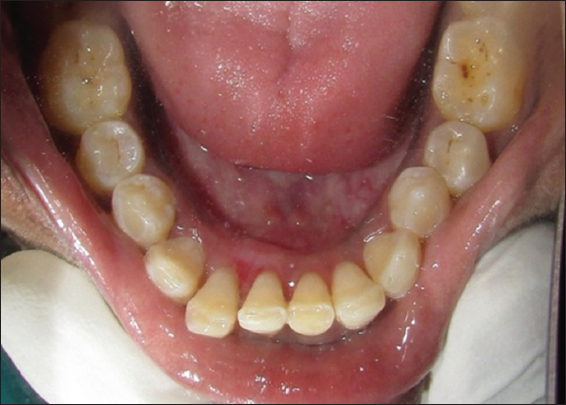

On the basis of history and clinical findings, a provisional diagnosis of irritation fibroma was given. The list of differential diagnosis included chronic fibrous epulis, peripheral giant cell granuloma, osteosarcoma, chondrosarcoma, pyogenic granuloma, and peripheral odontogenic fibroma. The investigations included complete hemogram, intraoral radiographs, and excisional biopsy of the lesion. Routine hematological investigation values were also found to be within normal limits. No radiographical changes related to the bone were seen [Figure 2]. As the patient reported discomfort during eating and while speaking, it was decided to go for an excisional biopsy performed under local anesthesia using a scalpel [Figure 3]. The excised tissue [Figure 4] was sent to the department of oral pathology for histopathological examination and H and E stained section revealed parakeratinized stratified squamous epithelium with elongated rete ridges. Irregular multiple foci of homogenous calcified areas were evident within the connective tissue. Thus, a final diagnosis of irritation fibroma was given [Figure 5]. Patient was recalled after 1 week for revaluation which shows satisfactorily healing and patient was asked to maintain oral hygiene [Figure 6]. No recurrence of fibroma was seen when patient was recalled after 6 months for follow-up [Figure 7].

Figure 7: 6 months post-operative